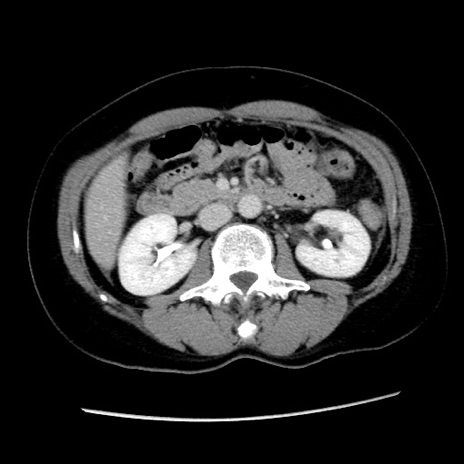

症例10(横断像)

【症例】 50歳代女性

【主訴】 腹痛

【現病歴】前日生レバーを食べた。今朝に排便あり。 昼前に突然発症の腹痛を生じ、当院救急外来を受診した。

【既往歴】 子宮筋腫にてで子宮全摘後

【身体所見】 意識清明、腹部:平坦、軟、下腹部やや左を中心に圧痛・反跳痛あり、筋性防御あり

【データ】WBC 7800、CRP 0.07